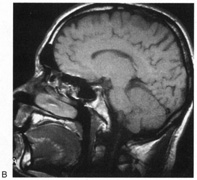

Fig. 15. Bilateral incomplete hemianopia. A 69-year-old man with decreased vision after prostate surgery. A. Fields show remaining central parafoveal vision with some sparing of inferior left quadrant. Note how the defect respects the vertical meridian. B. MRI shows bilateral medial occipital infarction, with sparing of the occipital poles, accounting for the macular-sparing bilaterally. (Courtesy of Dr. Lucia Vaina.)

Cerebral Blindness